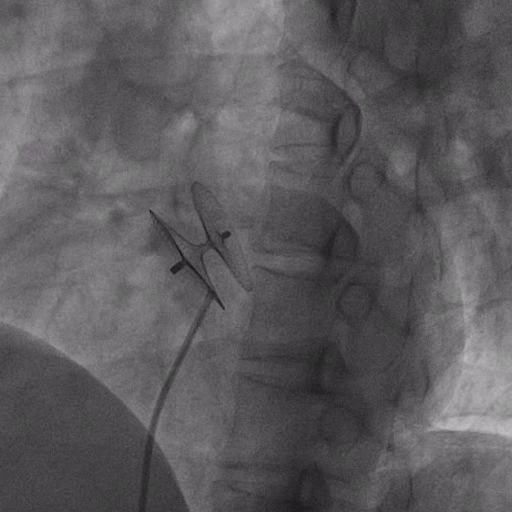

在獲得患者同意后,1月12日,尚福軍主任為患者進(jìn)行了PFO封堵術(shù)。術(shù)中造影可見(jiàn)封堵器殘余漏,尚福軍主任用精湛的技藝,順利通過(guò)封堵器殘余漏裂縫,將右心導(dǎo)管從右房送入左房,且順利到達(dá)肺靜脈;遂行卵圓孔未閉封堵術(shù)后殘余漏再次封堵;且完美釋放PFO封堵器,可見(jiàn)兩封堵器呈“馬蹄蓮”狀,再次術(shù)中造影未見(jiàn)殘余漏。